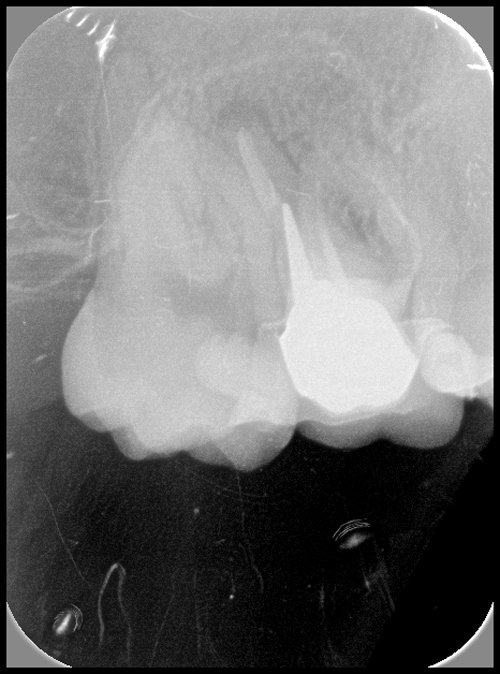

TRAITEMENT ENDODONTIQUE

Un traitement endodontique est réalisé lorsque des bactéries colonisent l’intérieur de la dent. Les canaux sont nettoyés selon un protocole précis. L’endodonte (intérieur de la dent) est ensuite obturé pour assurer la pérennité de cette désinfection (mécanique et chimique). Une fois les canaux remplis et étanches, un pansement provisoire est posé. La dent sera reconstituée de façon étanche et durable par le chirurgien-dentiste traitant. La dent sera reconstituée de façon étanche et durable par le chirurgien-dentiste traitant.

RETRAITEMENT ENDODONTIQUE

Même si la dent a déjà été traitée, elle peut se réinfecter. Plus le traitement est ancien et plus ce risque est important.

Parfois des insuffisances de nettoyage lors du traitement endodontique initial peuvent expliquer pourquoi une dent se réinfecte.